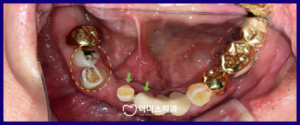

먼저 구강 내를

확인해 보았더니

위턱의 기존 틀니는 오래되어

형태와 적합이 불량한 상태였으며,

아래턱 잔존 치아들에도

우식과 치주 질환 등

다수의 문제가 발견되었는데요.

정밀한 검사를 위해

파노라마 사진을

촬영해 보았더니

✅️ 초록색 화살표 표시의

아래턱 양측 첫 번째 앞니는

치주 질환과

맞지 않는 위턱 틀니로 인해

치아가 위로 솟구쳐 올라와 있고

위아래 교합이 맞지 않는 상태였으며,

✅️ 노란색 동그라미 표시의

아래턱 오른쪽 첫 번째 작은 어금니(#43)과

송곳니(#33)는 우식이 심하고,

✅️ 빨간색 동그라미 표시의

아래턱 왼쪽 브릿지 보철물의 치아는

치주가 좋지 않았습니다.

또한 ✅️ 보라색 화살표 표시 부분은

치아가 상실된 상태였는데요.